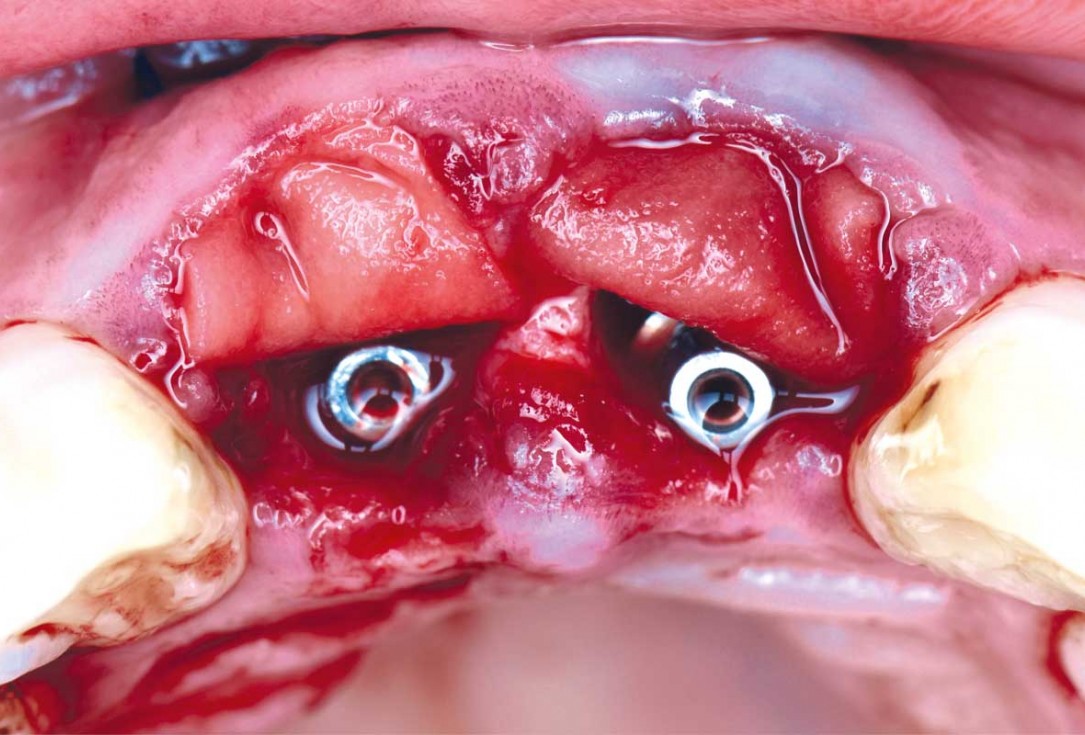

04/22 - Immediate implants are placed after extractioncerabone® and mucoderm® for immediate implantation in the aesthetic area - Dr. D. Robles